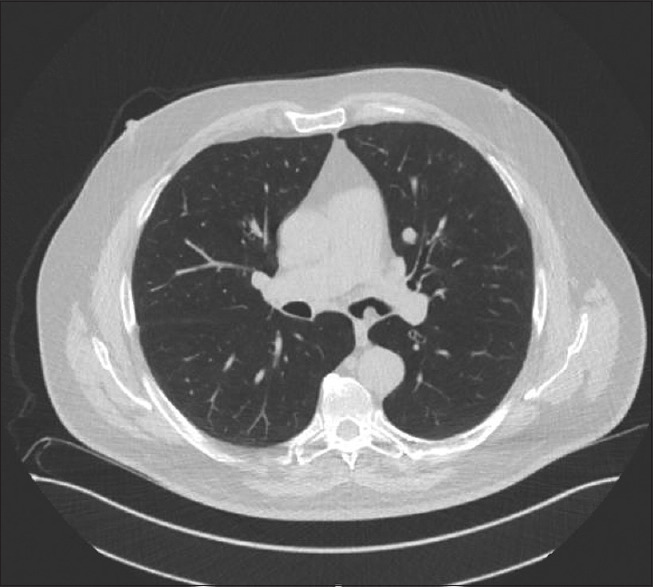

摘要错构瘤是一种常见的肺良性肿瘤。虽然大多数肺错构瘤位于肺实质内,但很少表现为支气管内肿瘤。我们描述了一例75岁的男性通过传统的柔性支气管镜切除支气管内错构瘤,另一例55岁的男性通过机器人导航支气管镜诊断支气管内错构瘤。我们还描述了过去13年中在我们机构诊断的支气管内错构瘤的其他三个病例的显著特征。随着先进的导航支气管镜技术的出现,我们预测支气管内错构瘤的鉴别率将会增加。

Abstract: Hamartoma is a common benign tumour of the lung. Although most pulmonary hamartomas are located within the lung parenchyma, rarely they present as endobronchial tumours. We are describing one case of a 75-year-old gentleman with endobronchial hamartoma removed via traditional flexible bronchoscopy and another case of a 55-year-old gentleman whose endobronchial hamartoma was diagnosed via robotic navigational bronchoscopy. We are also describing the salient features of three other cases of endobronchial hamartoma diagnosed at our institution in the last 13 years. With the emergence of advanced navigational bronchoscopy techniques, we predict that the incidence of identifying endobronchial hamartomas will increase.